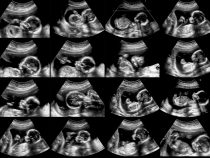

Nebezpečenstvá pred narodením

Pre zdravie človeka je nevyhnutný bezproblémový priebeh tehotenstva, pretože počas neho je telesný vývin najrýchlejší. V prvom trimestri tehotenstva vznikajú z jediného oplodneného vajíčka postupne všetky časti tela embrya. Tie sa v neskorších štádiách tehotenstva ďalej zdokonaľujú a rastú. Rýchlosť vývoja je však v rozličných… pokračuj